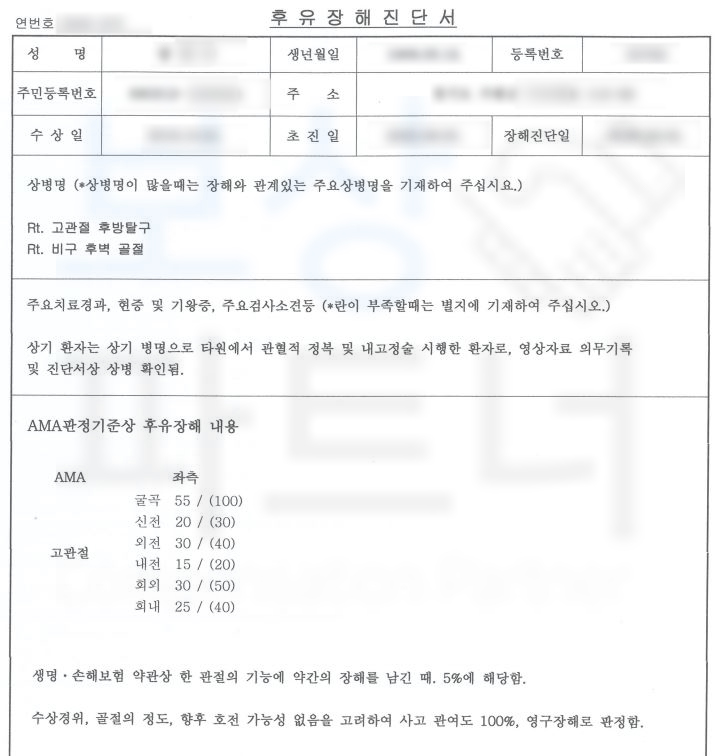

전문의의 후유 장해 평가를 받아

후유장해 보험금을 청구하는데요,

산재 장해 평가와는 약관이 다르기에

공신력 있는 대학병원의 전문의로부터

후유 장해 평가를 의뢰하였습니다.

피보험자는 고관절의 운동 장해 약간의 장해에 해당되어 5% 지급율, 영구 장해로 진단되었습니다. 보상 파트너는 대형 보험사를 상대로 피보험자의 장해를 인정받기 위해 손해 사정서 및 증빙자료를 보험사에 송부하였습니다.

물론 보험사에서는 약 2달간 평가된 장해가 과대평가되었다며 내부 의료자문을 시행하였지만 보상 파트너의 적절한 대응으로

피보험자의 후유 장애 담보 1억의 5%

총 500만 원의 후유장해보험금

지급받을 수 있었습니다.